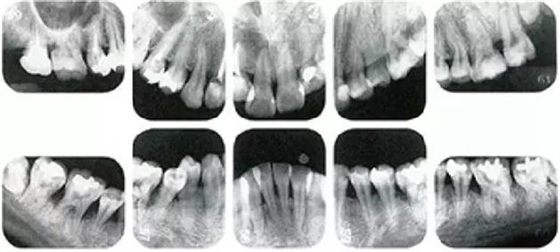

①的患者是35歲女性。4~10mm的牙周袋和大量的牙石。特別是在左上、右下、左下的磨牙處能看到大量牙槽骨吸收。這名患者是慢性牙周炎,僅在磨牙處有局部由風(fēng)險(xiǎn)因子導(dǎo)致(解剖學(xué)形態(tài))導(dǎo)致的重度病癥發(fā)展。

另一方面25歲女性的參考病例

②將會(huì)是什么樣的呢?左上、右下、左下的磨牙處有大量牙槽骨吸收,考慮到其發(fā)病年齡,斷定為是侵襲性牙周炎局部型。

●參考病例① 35歲女性

35歲女性。妊娠4個(gè)月。過(guò)去雖然接受過(guò)刷牙指導(dǎo),但菌斑控制狀態(tài)依然不理想?;颊哂邪l(fā)現(xiàn)自己刷牙時(shí)牙齦出血。

●參考病例② 25歲女性

25歲女性。菌斑控制狀態(tài)不好。齦溝除磨牙處外全在3mm以下,X光照片上左上、右下、左下的第一磨牙上有垂直性骨吸收。這個(gè)病例是參考病例①10年前的狀態(tài),是典型的侵襲性牙周炎局部型。